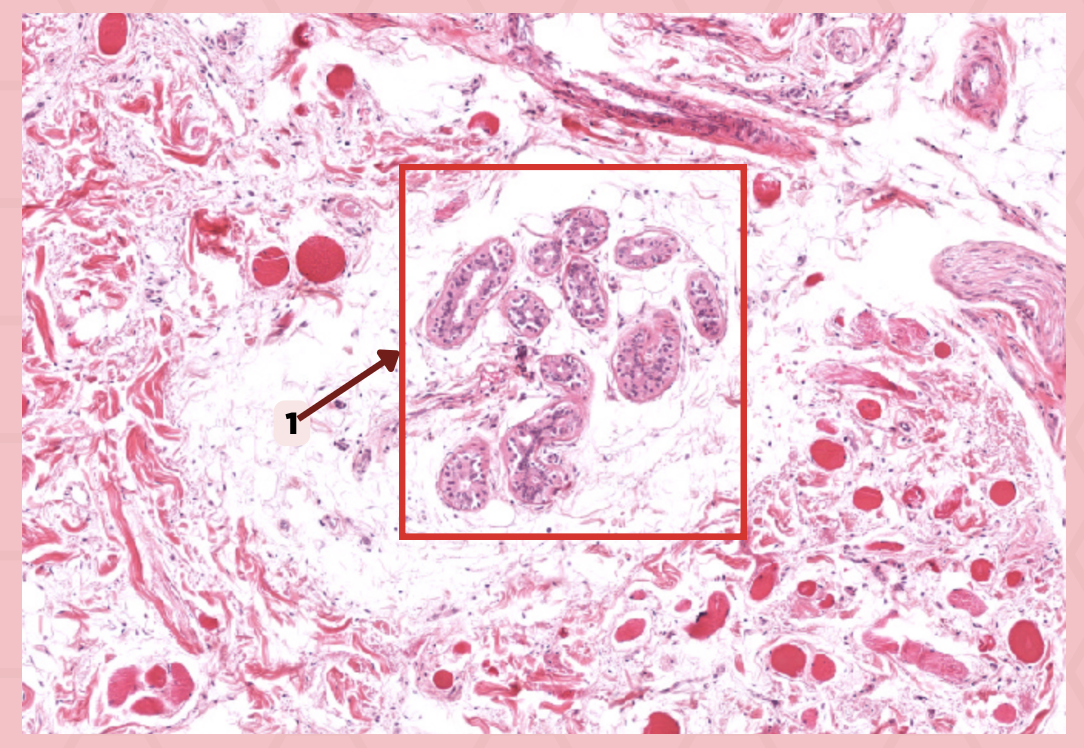

Cheek (Coronal Section)

Identify the specimen.

Hypodermis

Identify the structure labeled as 1.

Dermis

Identify the structure labeled as 2.

Epidermis

Identify the structure labeled as 3.

a. Keratinized stratified squamous epithelium

What is the lining of the structure labeled as #1?

a. Keratinized stratified squamous epithelium

b. Nonkeratinized pseudostratified squamous epithelium

c. Stratified squamous epithelium